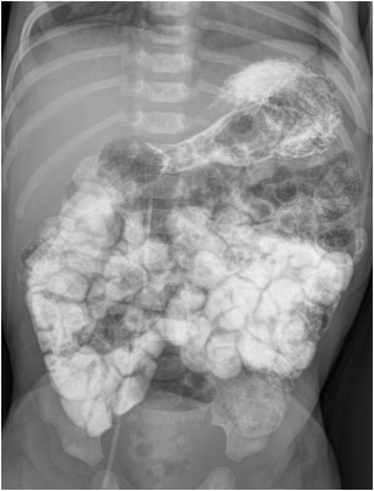

A 14-day-old male child with a history of frequent non-bilious vomiting since birth visited the emergency department. Vomiting persisted despite supportive treatments, such as positional changes and formula adjustments. The infant showed abdominal distension and had lost 5% of his birth weight. Physical examination revealed decreased skin turgor, and the patient produced only two wet diapers daily. Abdominal radiography revealed a distended stomach with some small bowel gas, while ultrasonography revealed duodenal dilatation. The upper gastrointestinal series revealed a windsock sign and a distended contrast-filled duodenum surrounded by a narrow lucent line with a small connection to the distal intestine (Fig. 1). No abnormalities were observed.

Fig. 1

An upper gastrointestinal series reveals a contrast-filled sac (arrow) with a surrounding rim of lucency. This configuration is referred to as the windsock sign, a typical imaging finding associated with a duodenal web.